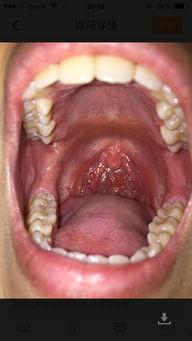

1. 过敏反应:有些人对白瓜中的某些成分过敏,如白瓜籽、白瓜皮等。一旦摄入,就会引起嗓子痛、喉咙痒等症状。

4. 农药残留:如果白瓜在生长过程中使用了过多的农药,残留的农药进入人体后,可能会引起嗓子痛。